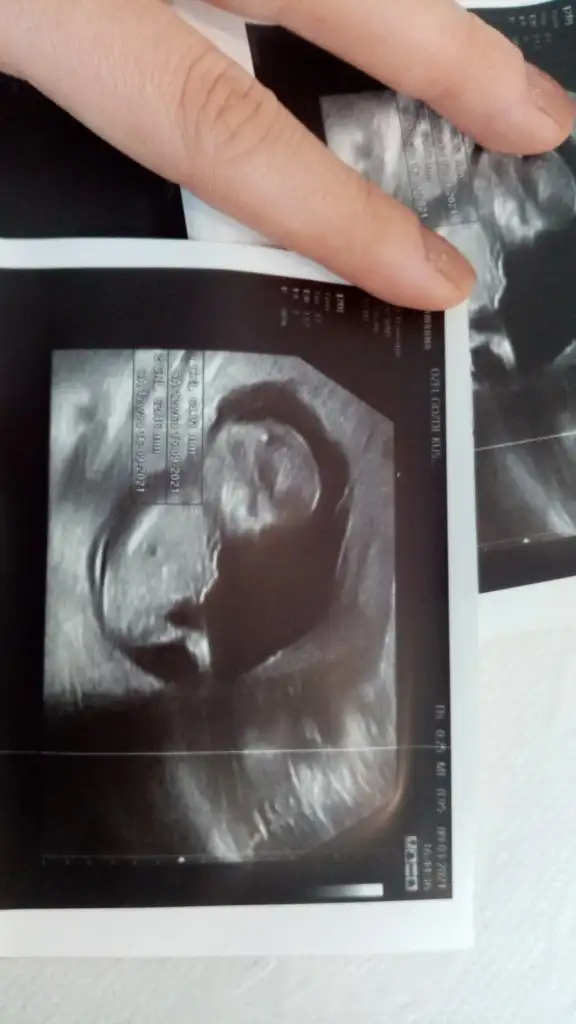

12. hAfta belli oluyor sonraki haftalarda netleştiriyorlar benim araştırdıklarımda ense ölçümü iyi olsa bile down olan var yada yanlış ölcülmüş ama burun kemiği ya gözükmüyor yada kısa riskli gebelik uzamanları bu dönemde kalbinide inceletledikleri için kalp deliği vb sorunlar da oluyor 20. HAftada kol bacak kısalığı ondanda anlıyorlar bebekte böbrek sorunlarıda oluyor yani kandan ayrı ultrasonda anlaşılıyor ha birde kan tesleri normal gelenlenlerde de down oluyor bu annneler genç üstelikSağolun kızlar. Ben bekliyordum zaten her şey aynı gidince kesin bu da riskli gelir dedim. Aslında ölçümleri kızımdan daha iyi. Değerler de daha iyi. Ama yaşımdan da yüksek çıktı herhalde. Yarın doktor yorumlayacak bakalım ne diyecek.